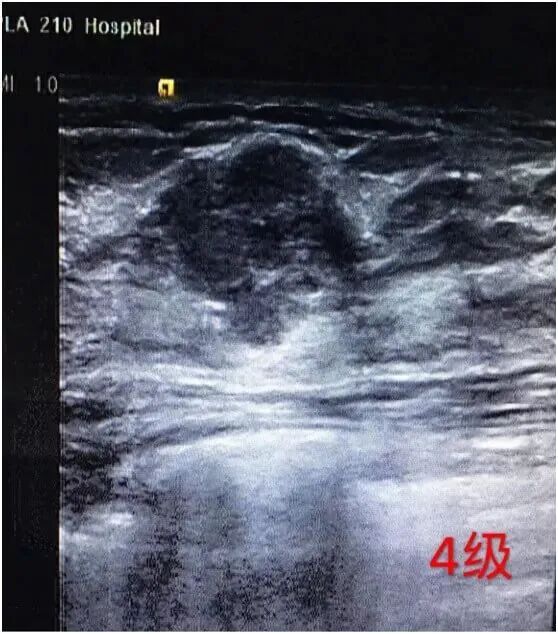

4级

考虑为恶性病变的可能比较大,恶性的危险性3~94%。 需要进一步检查明确诊断,比如穿刺病检或者取组织活检等。对影像诊断为IV级的,不管哪个亚级,有良性病理结果后均应定期随访。影像为IVC级的,病理穿刺为良性结果的,应对病理结果做进一步评价以明确诊断。